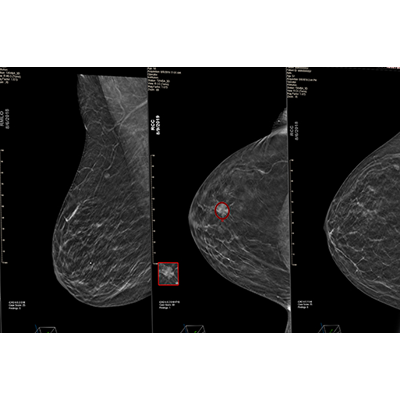

This next-generation AI solution, trained using advanced deep learning convolutional neural networks (CNN), offers advancements in cancer detection and specificity, achieving a 6.3% improved area under the receiver operating characteristic curve (AUC) over prior version, significantly improving the identification of hard-to-find and aggressive cancers while reducing false positives. This fourth-generation version introduces an option for clinicians to incorporate a prior exam into a current exam’s analysis.

Uncovers hidden cancers feared the most while reducing False Positives.

22%

improvement in finding hard-to-find cancers†

18%

improvement in cases with no marks†